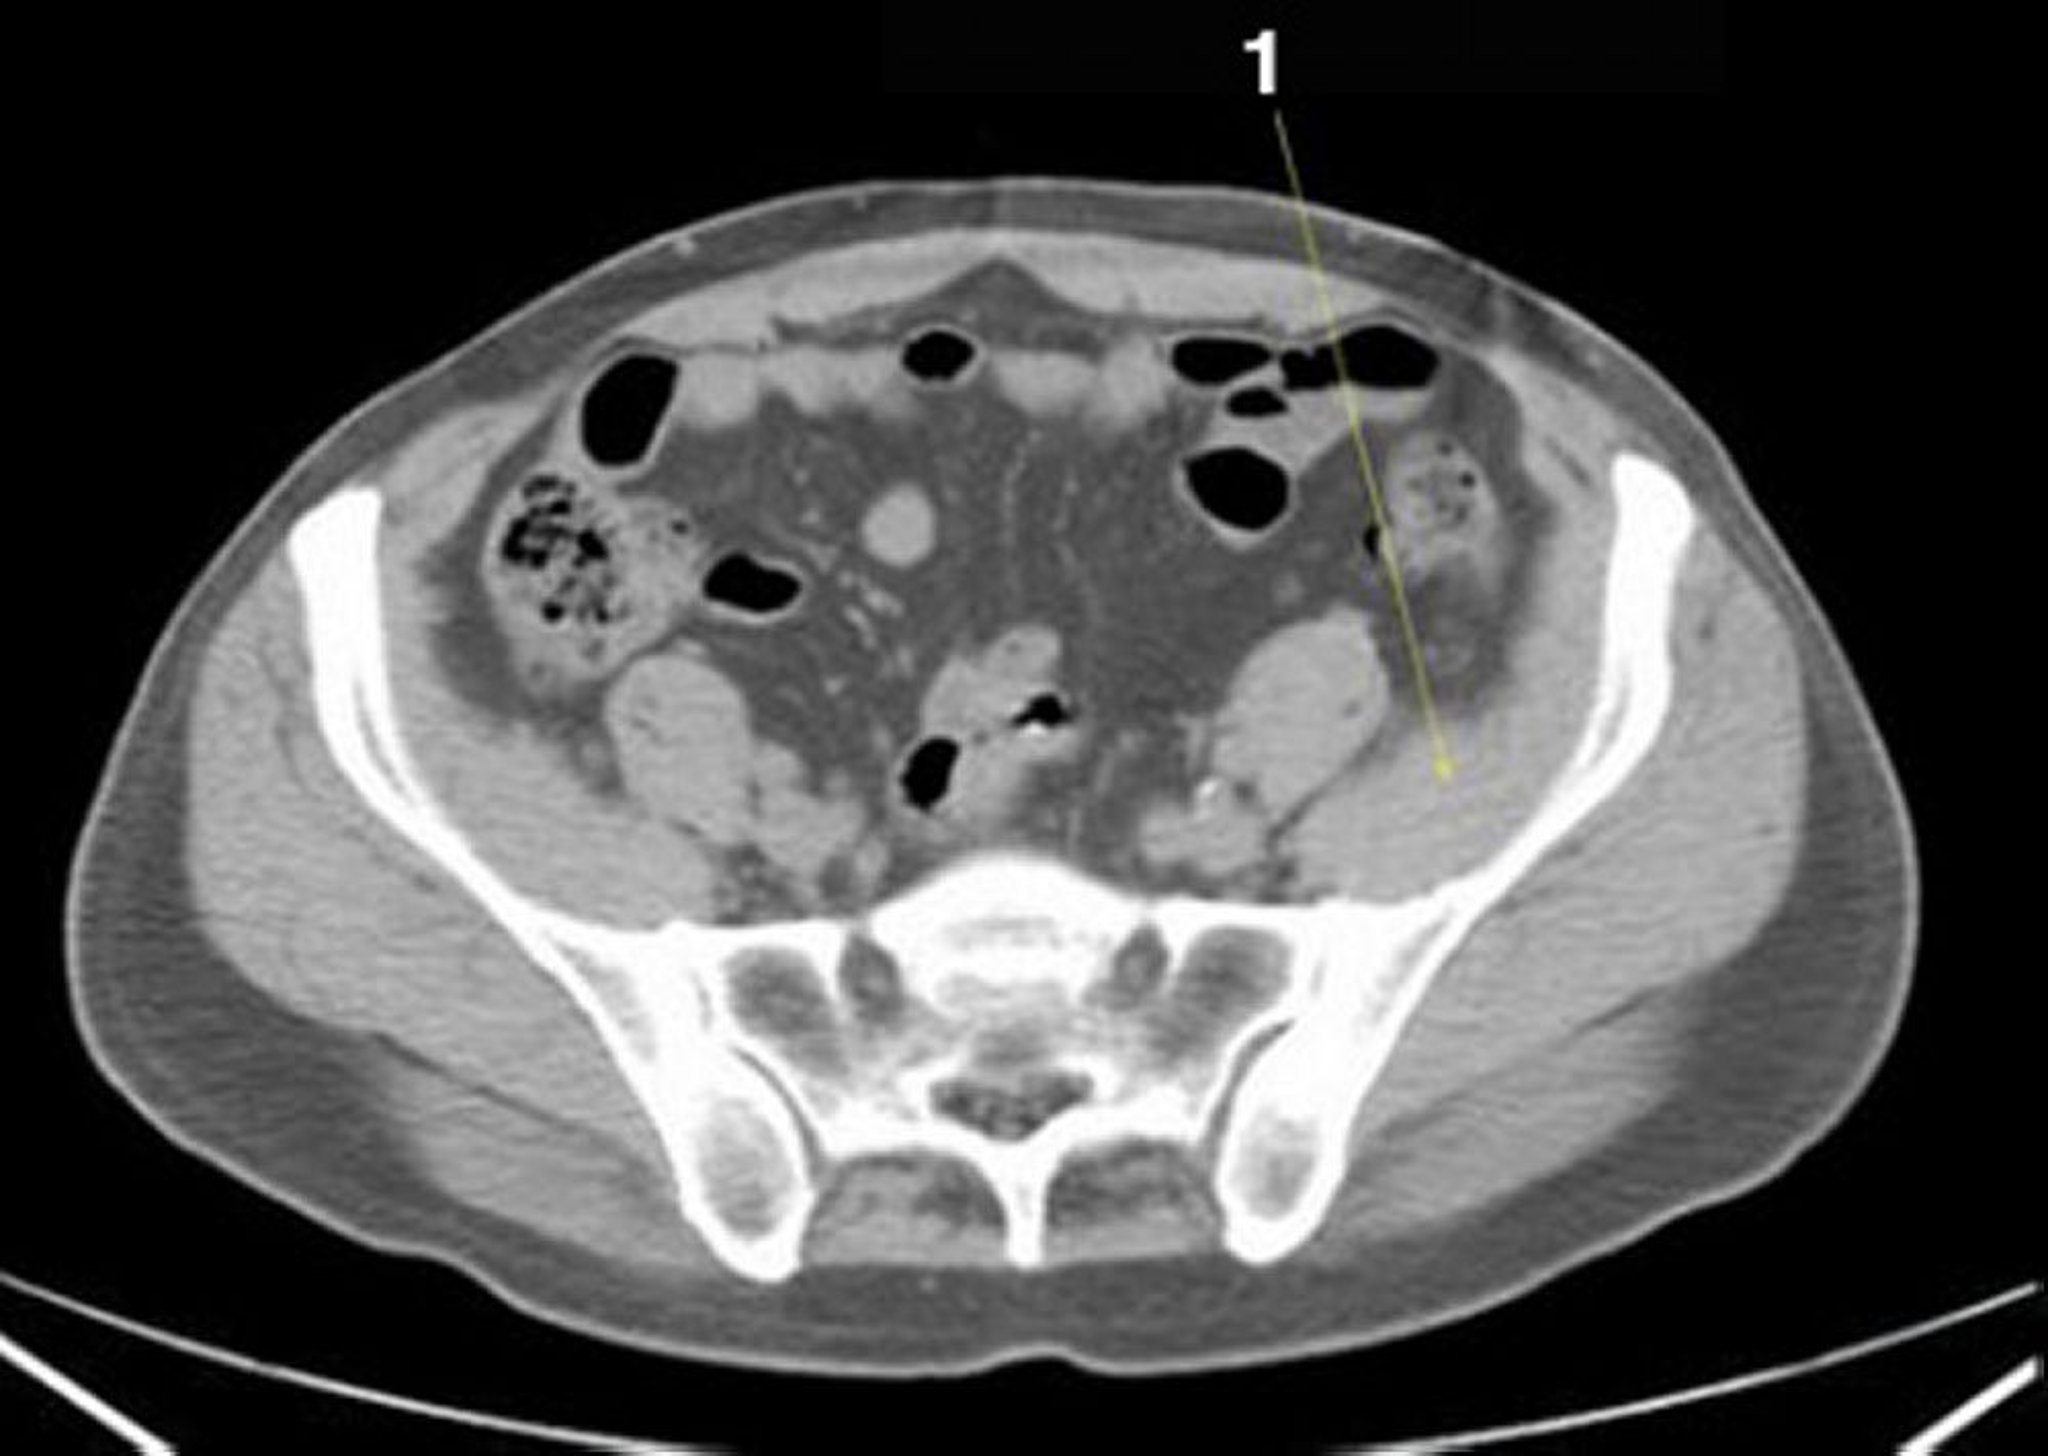

TC senza contrasto dell'addome e della pelvi che mostra un'anatomia normale (Slide 22)

1 = muscolo iliaco.